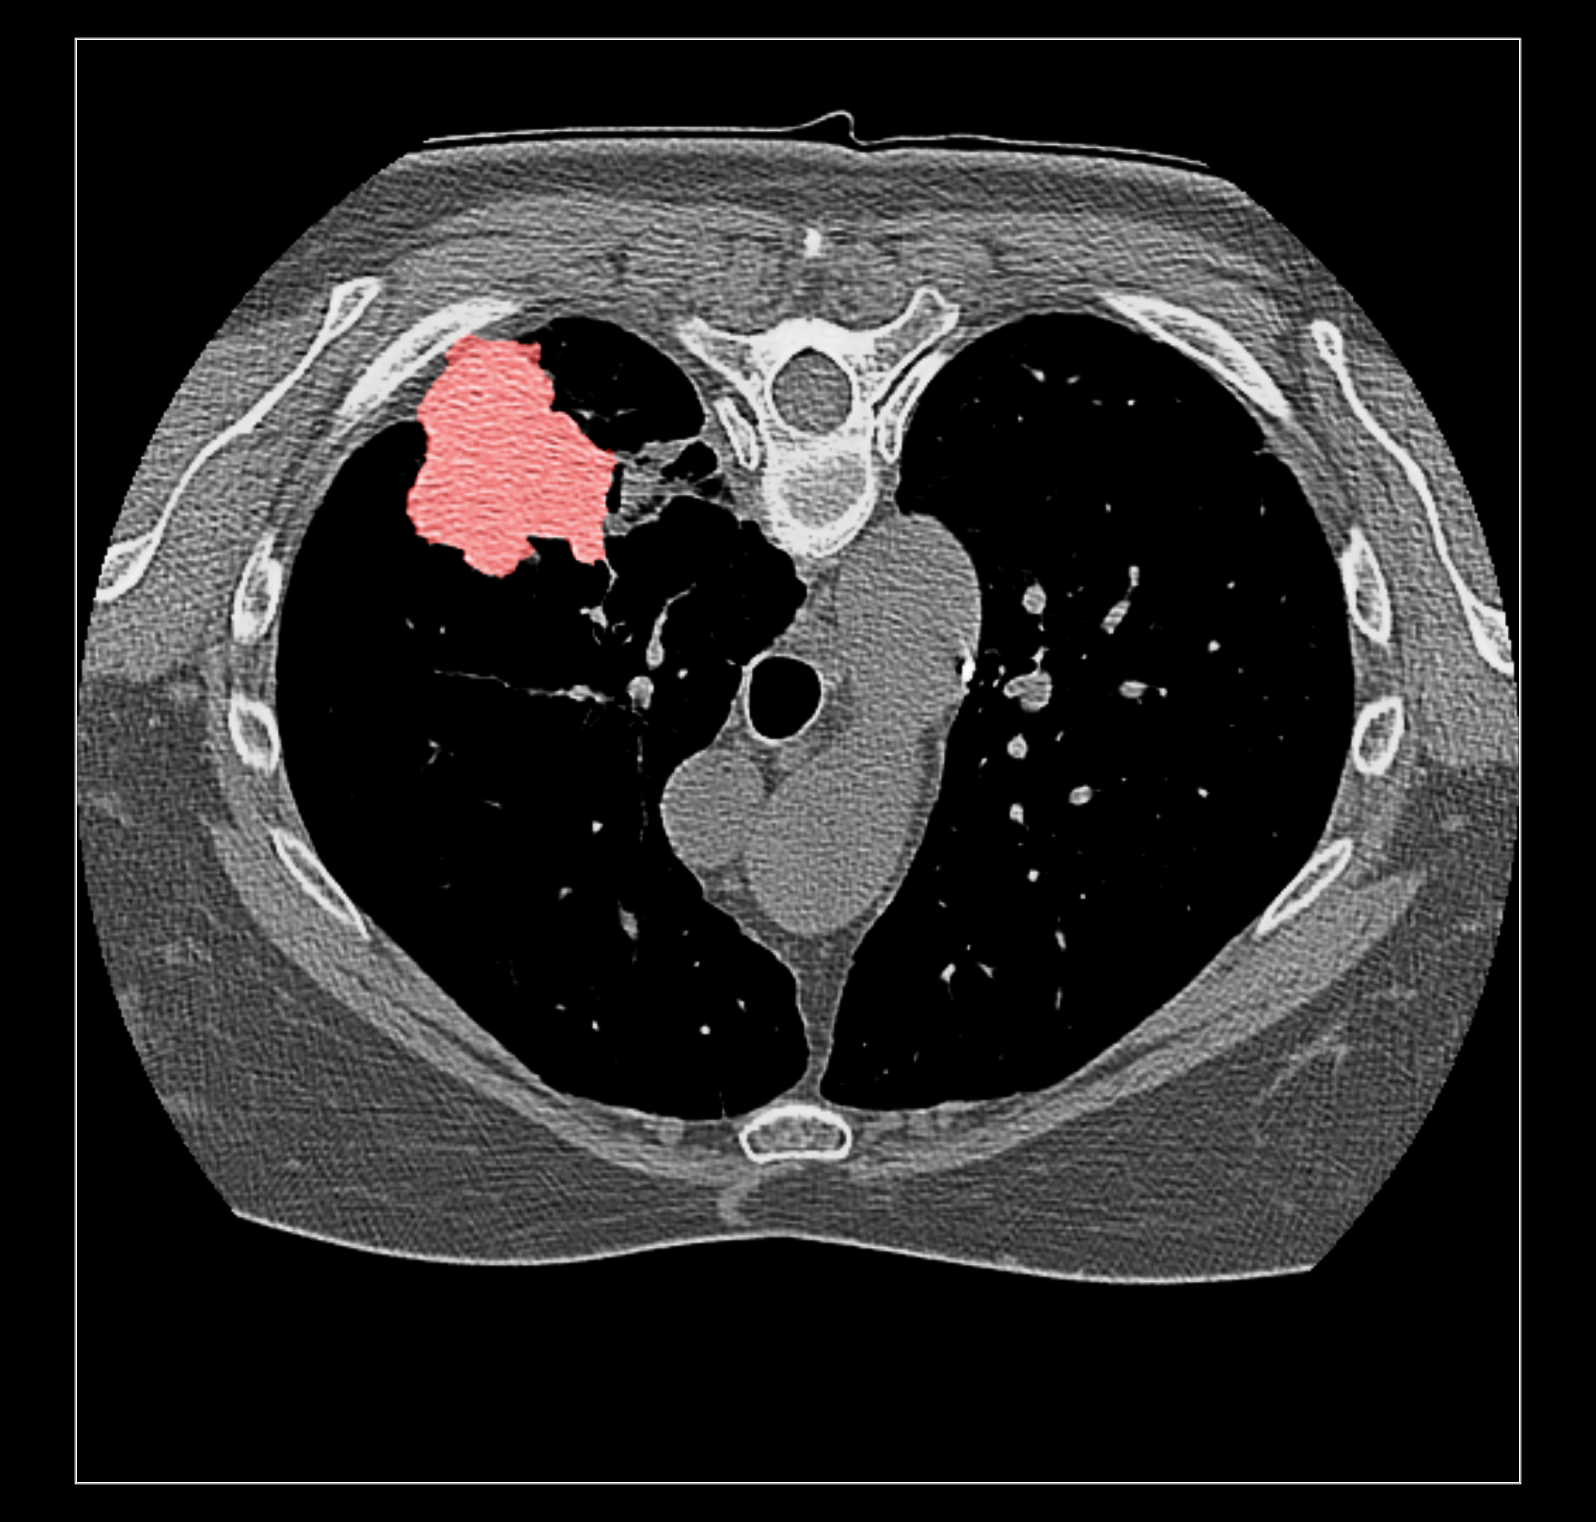

Surface rendering of a segmentation with image rendering of a CT scan can look ok, and only the outline of the surface can be shown using volume command "capFaces false". Showing both segmentation and CT as image also works fine if the brightness curve is not narrow. I've attached images for all 3 styles made with

The capped surface flickers badly when rotating because the surface cap is at exactly the same depth as the image plane so a rendering depth fight ensues.

The surface outline is so thin on a retina display it is hard to see. Currently we don't support thicker lines because thick line support was dropped in modern OpenGL.

The surface style with plane CT image display adjusts when the plane is moved with the slider since the CT and segmentations are grouped as multichannel volume data.